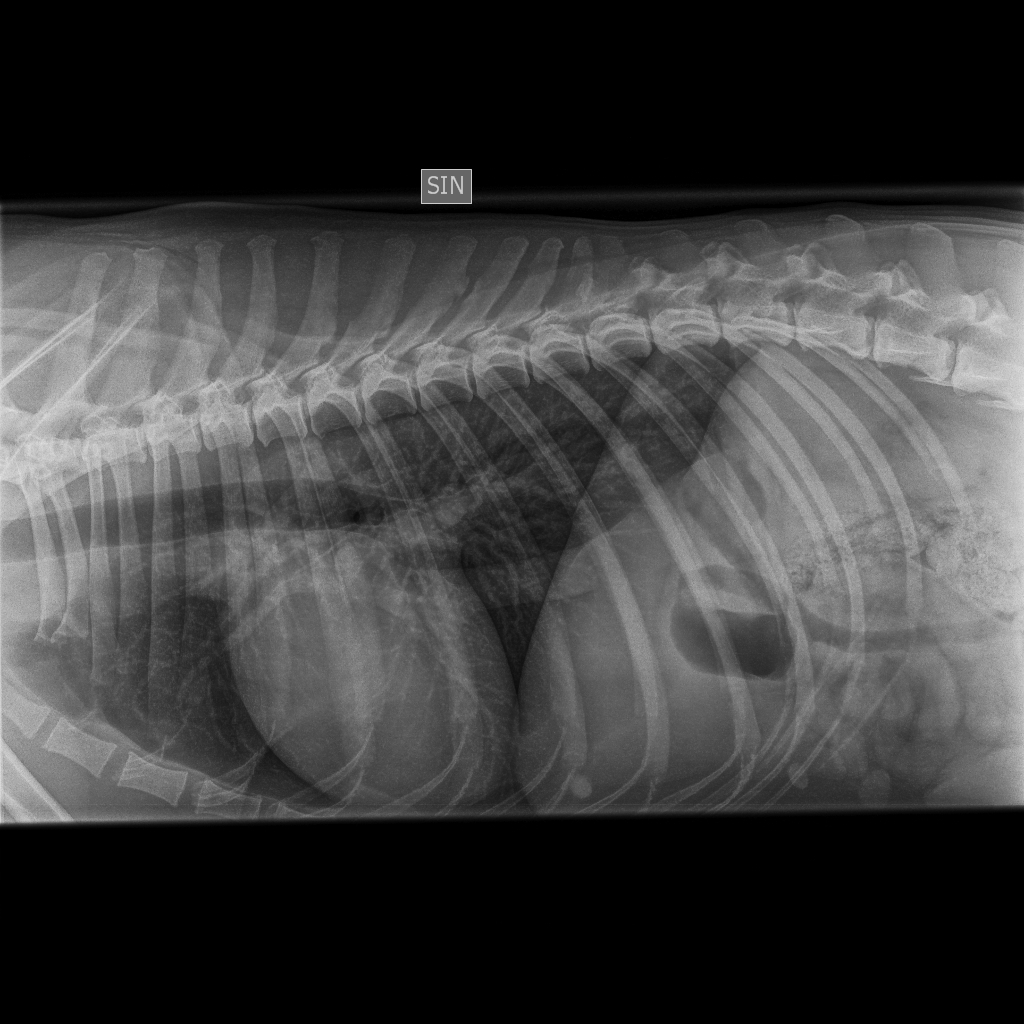

Lonkat |

A/A |

terveet |

B/B |

Kyynärpäät |

0/0 |

Viralliset selkäkuvat |

- |

Välimuotoinen lanne-ristinikama: LTV0 (normaali) |

*) 6 koiran (muut paitsi Pikimusta ja Parfyymi) luustokuvaukset tehtiin 19.3.10 ell Kari Ventelän toimesta.

Parfyymin

luustokuvaukset tehtiin 7.6.10 ell Hannu Pajulahden toimesta.

Kuvatuissa nivelissä ja selkärangassa ei havaittu muutoksia.